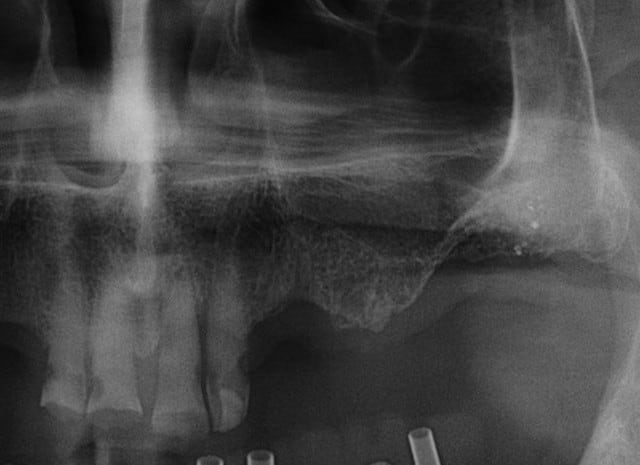

ce n'est pas fait dans l'ordre logique mais après la mandibule, le maxillaire... 12 à cassée (le patient pose sa prothèse pour dormir) donc je ne garde que 11/21/22 et pose d'implants.

A ce sujet, plutôt que de looker l'axe de 47, jette un œil sur 26 .... il ne s'agit pas de montrer que je suis le meilleur, mais que des techniques simples et bien raisonnées permettent d'obtenir des résultats corrects et reproductible, et ce par n'importe quel dentiste consciencieux.

pour 26 (comme pour les 17 autres implants de ce cas) flapless intégral (même pas de puch), foret initial directement à travers la gencive) et uniquement des éponges de Gelatemp là où c'était nécessaire.

je reprends le sujet 26, car il est certain que ça ne rentre pas dans la logique du soulevé de sinus, mais que l'abord latéral aurais été plus sur.

et pourtant le résultat ne me déplait pas(entre septembre 2015 et Mars 2016)